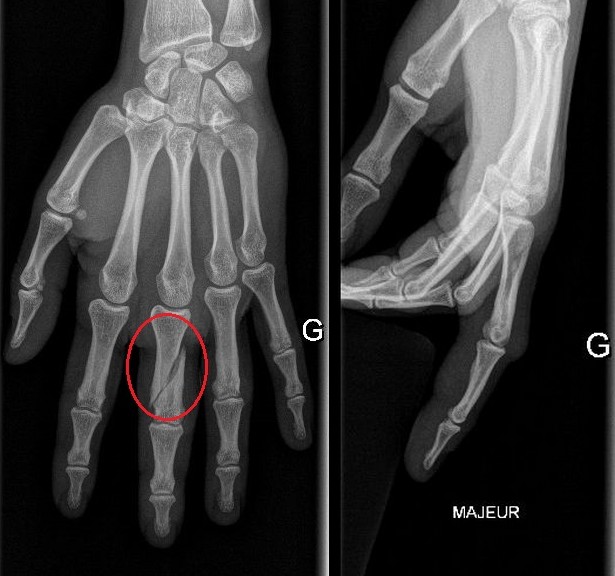

Phalange Cassée Petit Doigt. Un Jour En Chirurgie Orthopedique Et Traumatologique Fracture déplacée de la première phalange Chacun d'entre eux est constitué d'os qu'on appelle les phalanges Il peut être plus facile de repérer un désalignement ou une torsion sur les doigts extérieurs comme le petit doigt, l'index ou le pouce.

Doigt cassé Banque de photographies et d’images à haute résolution Alamy. Les fractures des phalanges, communément appelées fractures des doigts, sont des blessures courantes traitées. Les symptômes et le traitement d'une fracture de la phalange dépendent de la localisation et de l'intensité de la blessure.